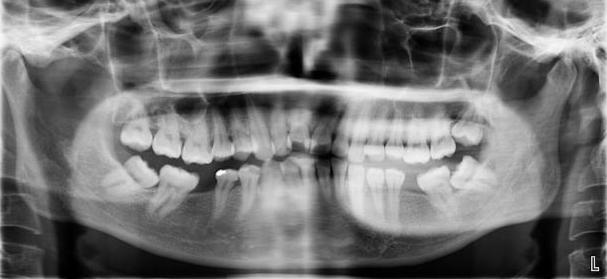

牙齿矫正,其原理就是牙槽骨改建的过程,利用的就是牙齿移动、牙槽骨跟随生长的机制。具体做法就是医生通过矫治器给牙齿施加一个外力,牙齿就会在牙槽骨里缓慢移动,受力侧牙槽骨吸收,受到牵引的一侧牙槽骨增生,以保持牙槽骨正常厚度。此消彼长,所以牙齿是不会松动的。PART 02